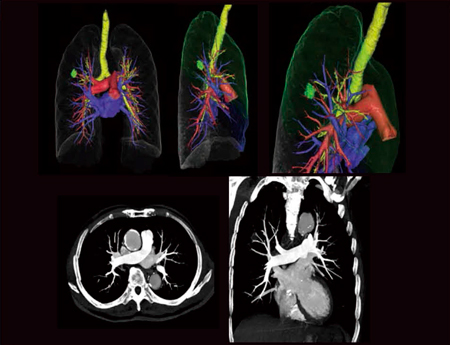

General部門

中森克敏

(三重大学医学部附属病院中央放射線部)

【背 景】83歳,男性,右上葉肺がん。右上葉切除予定につき術前精査,3D-CT希望。

【所 見】右肺上葉S2に最大径18mmの充実性結節を認める。右原発性肺がん:cT1aN0M0。

【ポイント】肺動静脈分離3D-CTの多くは肺動脈相,肺静脈相を含む多時相撮影が広く用いられている。当院では造影剤を2段階注入することにより,肺動静脈間にCT値差をつけ,1相撮影にてVR作成を容易にし,多時相撮影に比べ大幅な被ばく低減を実現している。わずか数秒の肺循環をとらえるには,Flash Spiralが最適であり,全肺が約1秒で撮影できる。

また,管電圧を100kVにすることで,コントラストを高くするとともにさらなる被ばく低減も可能にしているが,IR法により線量不足の印象はなく,画質を担保できる。1相撮影に必要な造影剤量は約40mLで,腎機能低下症例に対しても負担が少ない。時相の違いによる位置ずれのない良好なVR画像で肺動静脈のバリエーションを評価でき,手術時間の短縮にもつながっている。また,アキシャル画像で肺動静脈間にCT値差があるため,同一画像上にて両者が識別可能で読影の手助けにもなっており,ルーチン業務に本撮影法を取り入れている。